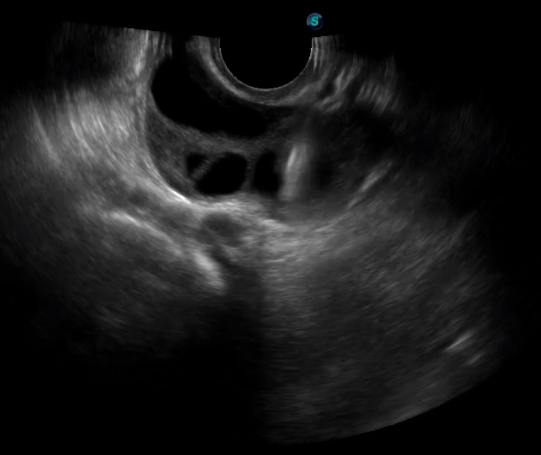

取卵臨床圖

傳統(tǒng)腔內(nèi)探頭采用直柄設(shè)計,在搭配穿刺架使用時,手術(shù)空間小,不易操作;生殖專用的曲柄探頭,探頭柄采用彎曲成角度設(shè)計,可實現(xiàn)監(jiān)視、取卵兩不誤,搭載穿刺架時,可以清晰顯示穿刺針的進針過程、深度和位置,實時監(jiān)視取卵全過程,保障取卵操作精準(zhǔn)與安全。